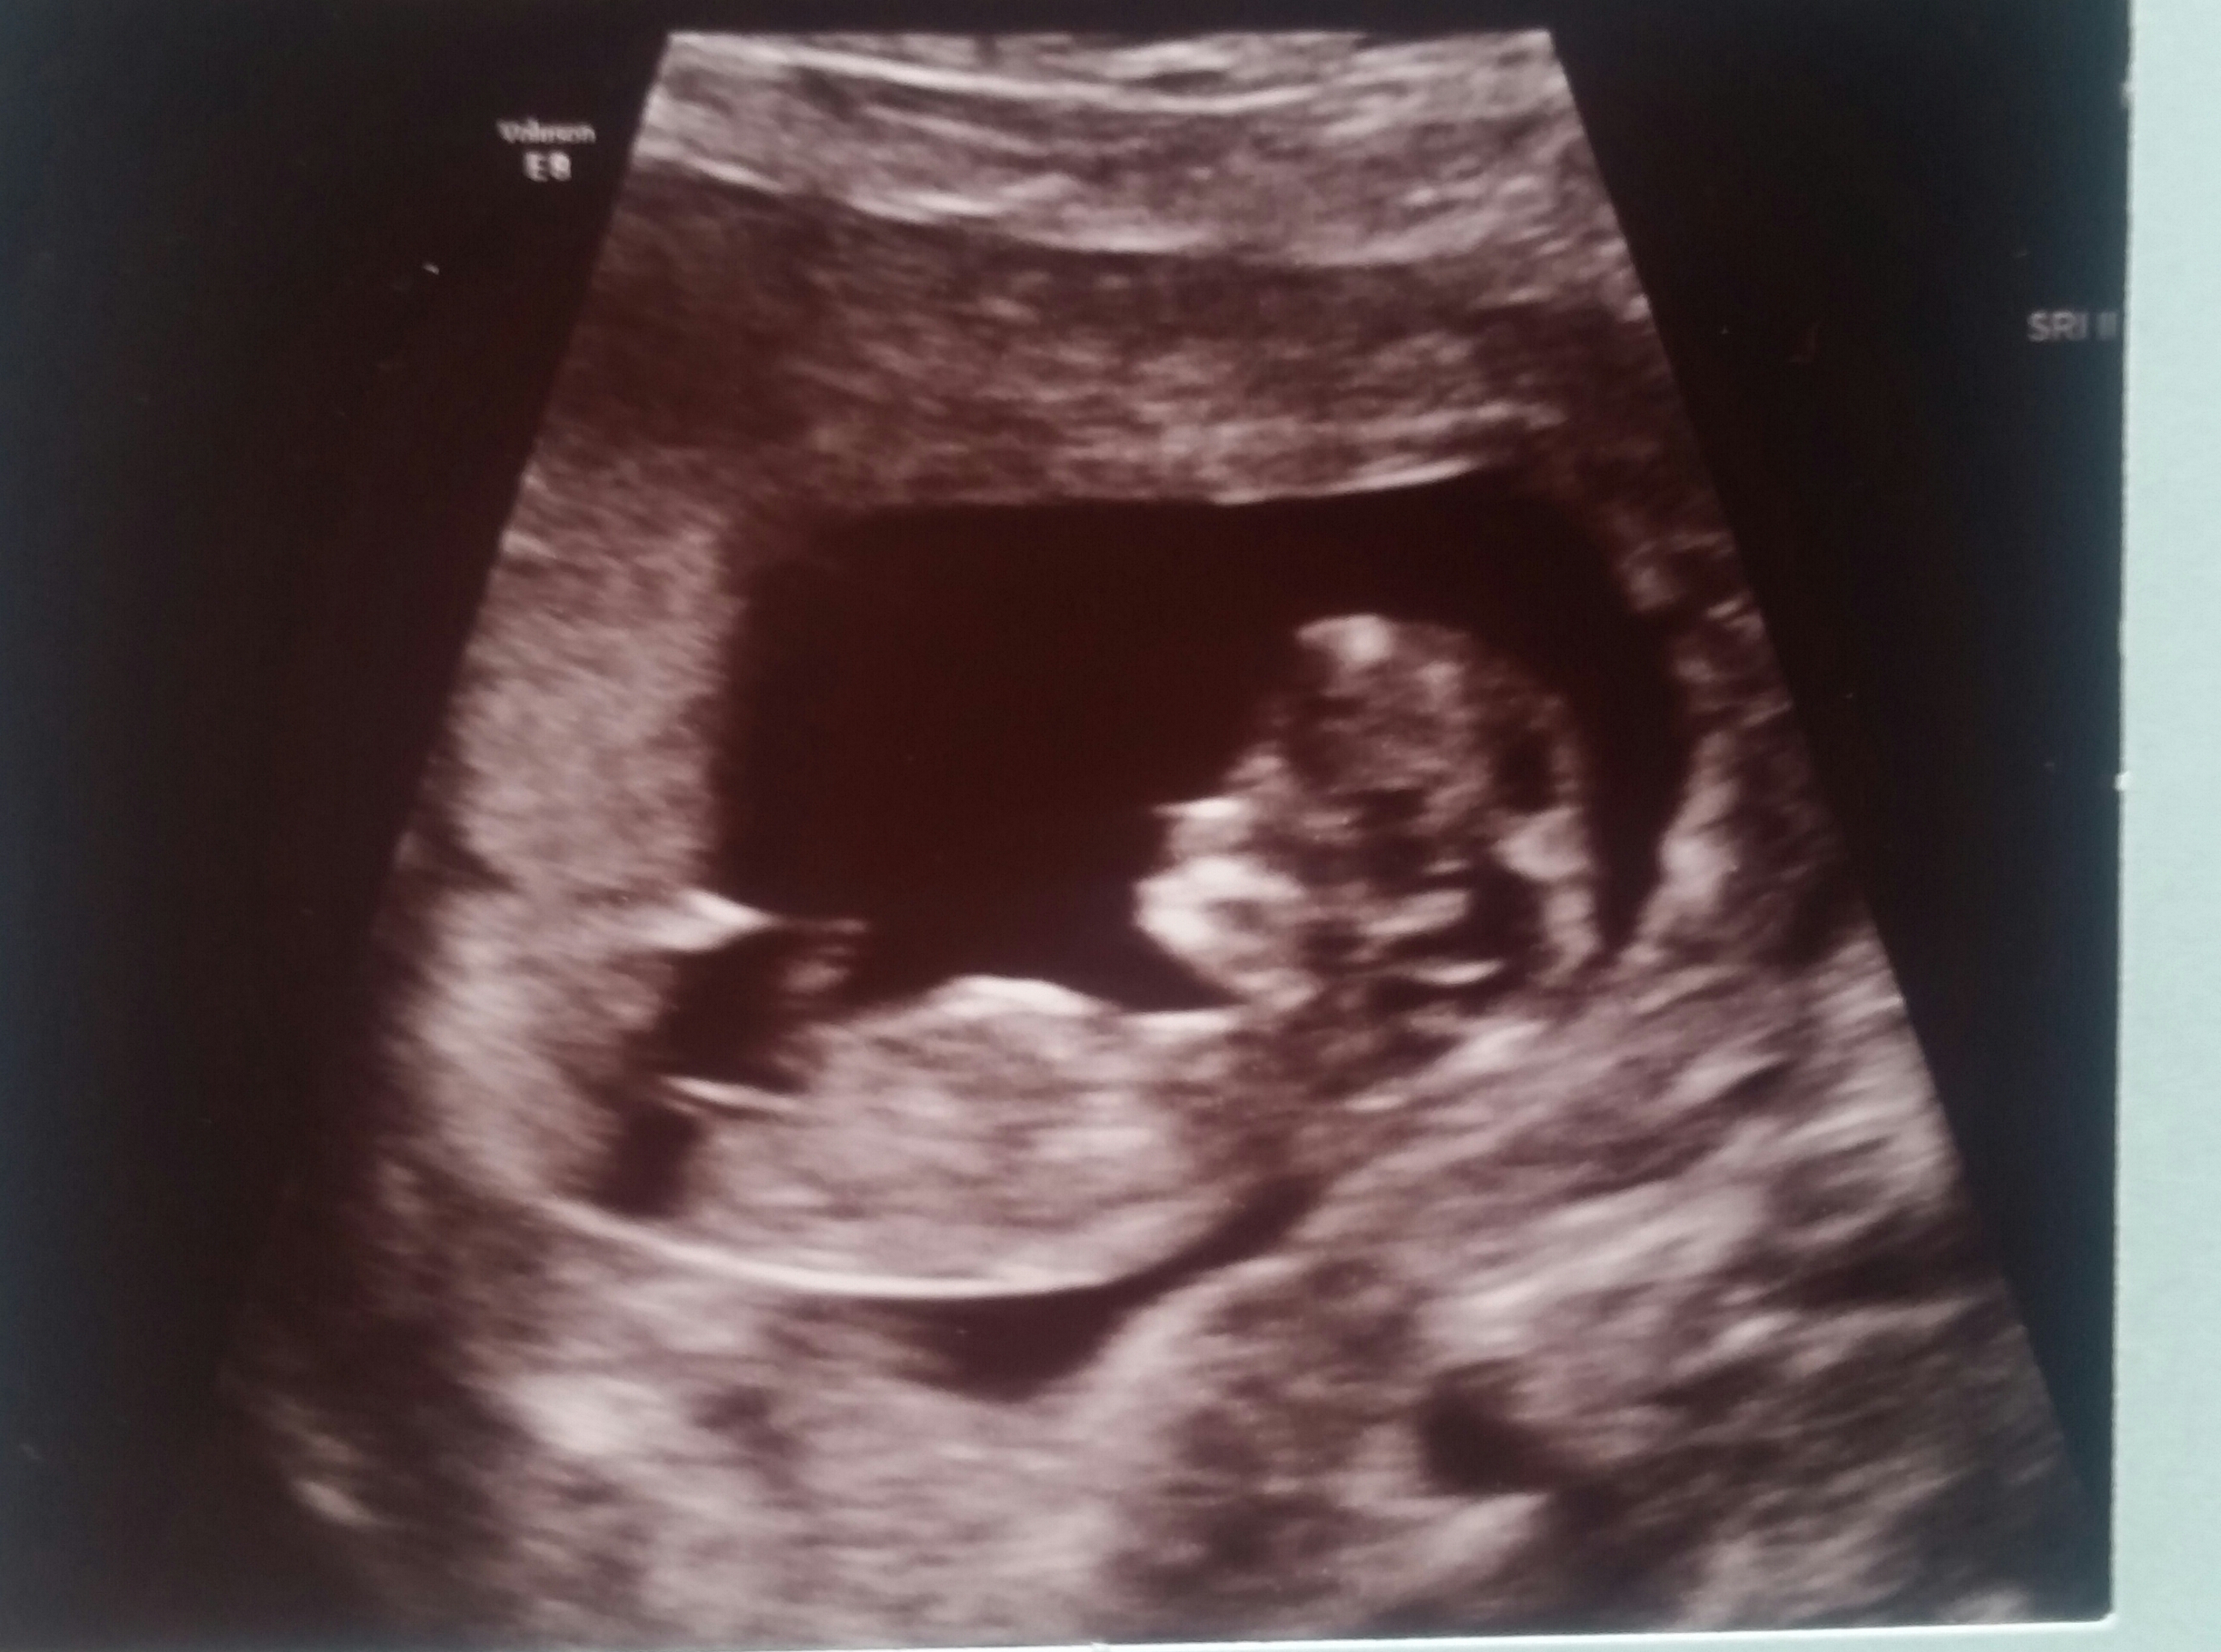

Would people who know about nub theoAttachment 32489theory like to take a guess at my baby's gender. 11 weeks 1 day